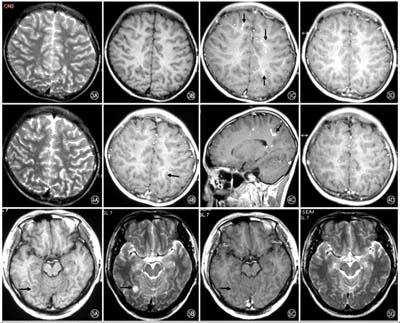

Về mặt chẩn đoán, chụp cộng hưởng từ (MRI_Magnetic resonance imaging) trên một bệnh nhân mắc bệnh Agiostrongyliasis thường có biểu hiện hình ảnh tăng nhiều nốt nhỏ trong nhu mô não và tăng tuyến tính trong phần vùng màng mềm bao bọc quanh não và tủy sống. Độ phân giải hoàn toàn của các hình ảnh MRI bất thường xảy ra điển hình sau 4 - 8 tuần. Hình ảnh đa nốt cũng được phát hiện trên phim chụp MRI của nhu mô phổi, điều này có thể phản ánh có sự hiện diện giun trong các cơ quan phủ tạng.

H5